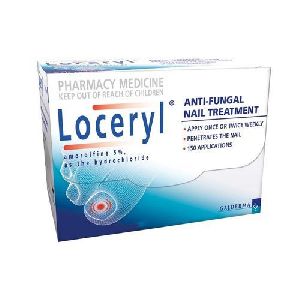

Amorolfine 2.5 Medicated Nail Lacquer

120 - 320 Per Box

Loceryl Nail Lacquer

Loceryl is used to treat fungal infections of the nails. Loceryl contains the active ingredient amorolfine (as the hydrochloride), which belongs to a group of medicines known as antifungals. It kills a wide variety of fungi that can cause nail infections.